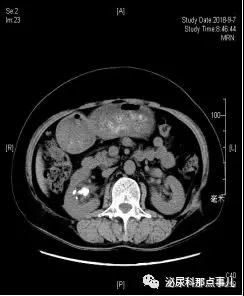

术前CT

术后CT